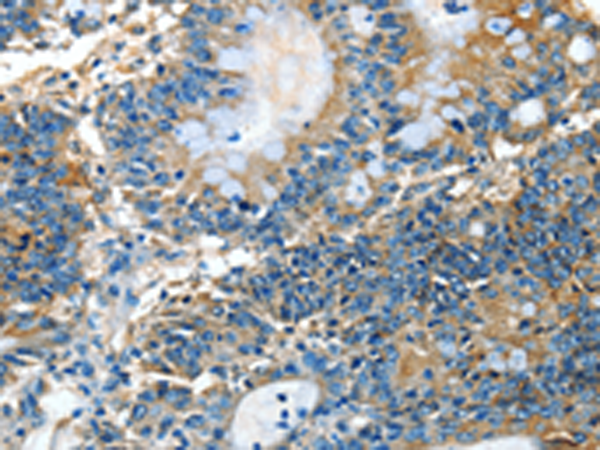

分类: 科研抗体货号: P07783别名: ADCK4; NPHS9应用: IHC反应种属: Human, Mouse, Rat